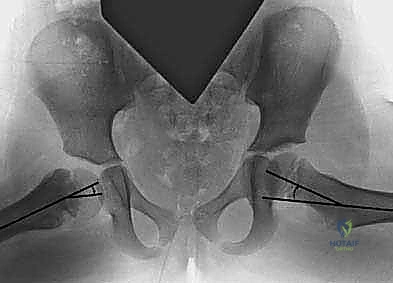

الميكانيكا الحيوية وزاوية هيلجنراينر (HEA)

لتقييم مدى خطورة الحالة واحتمالية تفاقمها، يعتمد الأستاذ الدكتور محمد هطيف على قياسات دقيقة جداً من صور الأشعة السينية، وأهمها "زاوية هيلجنراينر-المشاشية" (Hilgenreiner–epiphyseal angle - HEA).

تُقاس هذه الزاوية بين خط هيلجنراينر (خط أفقي وهمي يمر عبر غضاريف النمو الثلاثية في الحوض) وخط مائل موازٍ لصفائح النمو القريبة لعظم الفخذ.

- إذا كانت زاوية HEA أقل من 45 درجة: غالباً ما يصحح التشوه نفسه تلقائياً مع النمو، ويكتفي الطبيب بالمراقبة الدورية.

- إذا كانت زاوية HEA تتراوح بين 45 و 60 درجة: هذه منطقة رمادية (Gray Zone). يتطلب الأمر مراقبة سريرية وشعاعية دقيقة كل 3 إلى 6 أشهر لملاحظة أي تقدم في التشوه.

- إذا كانت زاوية HEA أكبر من 60 درجة: هذا مؤشر حاسم وخطير. يعني أن قوى القص تتغلب على قوى الضغط، وأن التشوه سيتفاقم حتمًا وبسرعة. في هذه الحالة، التدخل الجراحي (تقويم الفحج) ليس خياراً، بل هو ضرورة طبية عاجلة لإنقاذ المفصل.

2. قياس زاوية هيلجنراينر (HEA) لتحديد خطة العلاج (هل تحتاج جراحة فورية أم مراقبة).